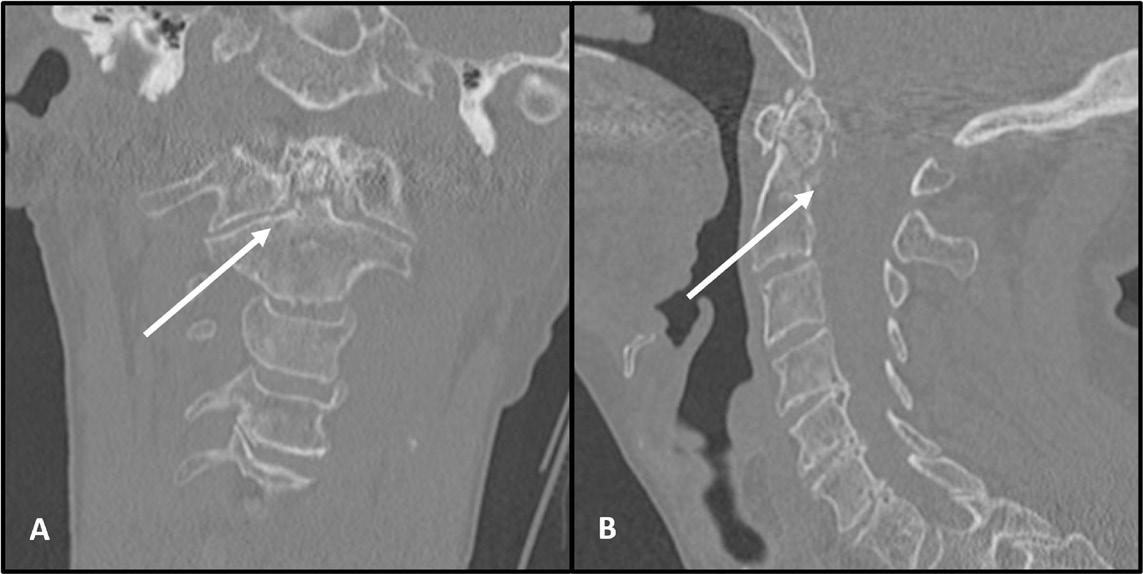

FIGUR 3: CT av densfraktur type II, coronal snitt (A) og sagittal snitt (B). Samtykke innhentet fra pasient.